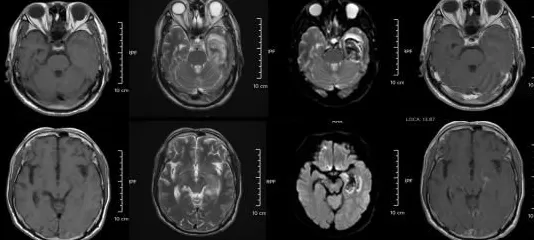

△某单纯疱疹病毒性脑炎患者的医学影像。图源:浙江大学医学院附属第二医院

但如果拖延治疗,甚至会引发脑炎,可能出现癫痫、肢体偏瘫、尿潴留、认知功能障碍等严重后遗症,恢复时间长达 3-6 个月,甚至影响终身。